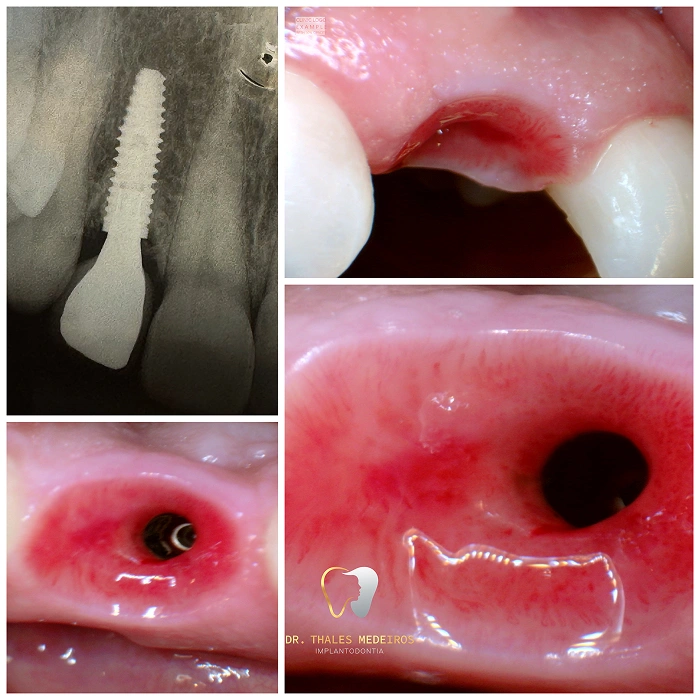

Implantes Dentários: Sorrisos restaurados com segurança e precisão

Recupere seu sorriso e sua qualidade de vida com os implantes dentários do Dr. Thales Medeiros. Com 9 anos de experiência e quase 2.000 implantes realizados, ele é referência na Paraíba em reabilitação oral. Os implantes proporcionam benefícios como restauração da mastigação, preservação da estrutura óssea, estabilidade dentária duradoura, melhora da estética do sorriso e aumento da autoestima.

Cada procedimento é planejado de forma personalizada, unindo tecnologia de ponta e cuidado humanizado para oferecer resultados seguros e naturais.

Cirurgia Plástica Periodontal e Periimplantar

Recupere a estética e a saúde do seu sorriso com a cirurgia plástica periodontal e periimplantar. O procedimento corrige retrações gengivais, remodela os contornos e prepara o sorriso para implantes e facetas. Entre os principais benefícios estão gengivas mais saudáveis, sorriso simétrico, harmonia estética e aumento da autoestima, garantindo resultados naturais.